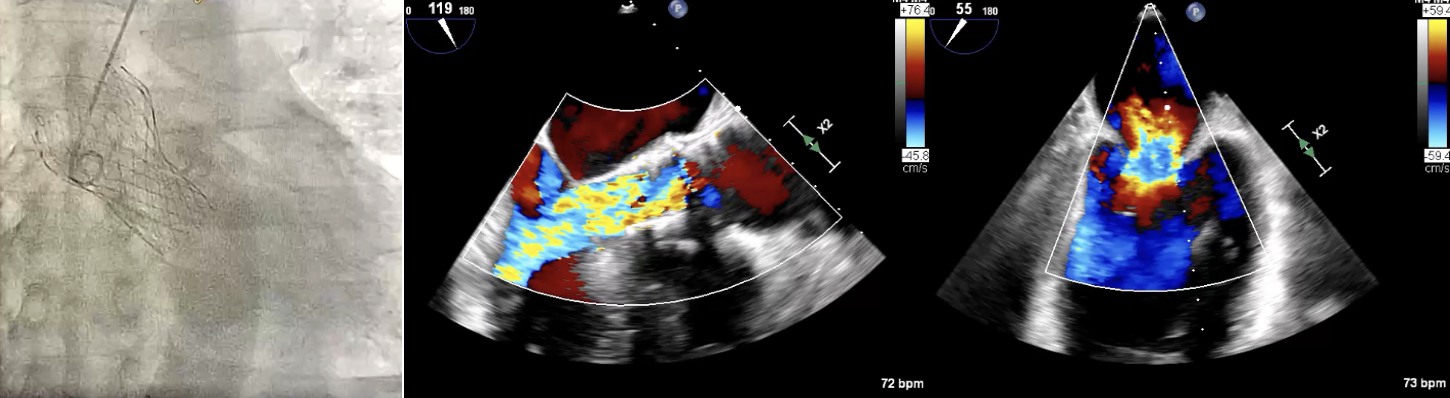

A 79-year-old male, who underwent TAVI with a 29 mm CoreValve in 2015, presented six years later with NYHA class III symptoms. Echocardiography showed Severe central AR and severe functional MR with Mean gradient: 12.4 mmHg; peak gradient: 23.3 mmHg, AVA: 1.4cm2 and LVEF: 61%. EuroSCORE II was 7.00% and STS score was 3.060%

To mitigate the risk of coronary obstruction, the RCA was protected using a coronary guidewire and balloon. CT confirmed absence of commissural misalignment of failed CoreValve, and commissural alignment of the Evolut PRO was achieved by orienting the delivery system with the flush port at 3 o¡¯clock. The inflow portion of the the Evolut PRO was implanted at the same level as the failed CoreValve. Aortography post-implantation confirmed no RCA obstruction, allowing safe removal of the guidewire and balloon. The procedure was uneventful, with no conduction disturbances or paravalvular leak. The functional mitral regurgitation resolved immediately after the procedure.